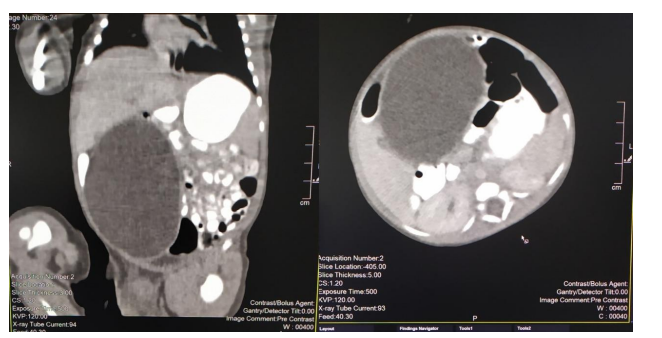

Figure 3. Gross macroscopic specimen

A 2815g 5-day-old male patient was born at 37.5 weeks gestation with an APGAR score of 9-10-10. An ultrasound scan identified an intra-abdominal lesion, suggesting a megacolon diagnosis. After birth, further investigations revealed a large extrahepatic unilocular fluid-filled structure measuring 80x30 mm, indicating a mesenteric cyst, cystic lymphangioma, or composite hepatic hamartoma. A cystic mass attached to the terminal ileum was noted at laparotomy, and the cyst and intestine were closely related. The ileon-cyst complex was resected, and end-to-end interrupted primary anastomosis using vicryl 4/0 was performed. The gross pathological specimen showed a 75x10 mm intestinal fragment with ileal mucosa of normal appearance joined to a 80x35cm cystic structure containing mucus without luminal communication. The cyst contained mucus covered by glandular epithelial tissue and shared musculature with the intestinal portion, covered by gastric tissue. The cystic structure shared musculature with the intestinal portion, covered by gastric tissue within normal histological limits. According to the Long classification, the specimen was classified as Type 1B intestinal duplication. The patient's post-operative period was uneventful; at six months, he is thriving well without any complications.